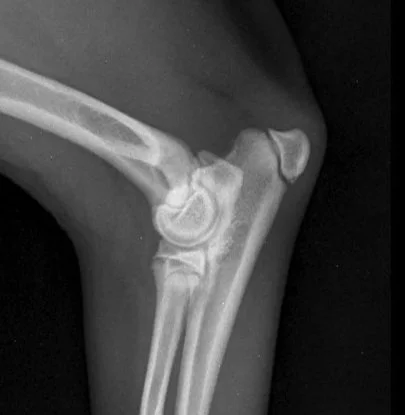

Early Diagnosis of Hip & Elbow Dysplasia in Dogs

Hip and elbow dysplasia are the most frequent skeletal orthopedic diseases affecting growing dogs.

Early detection of the disease is crucial to be able to modify the development of the affected joint and limit the progression of the disease and cartilage damage.